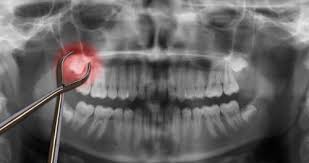

The total tooth extraction healing time depends on the location of the tooth and the type of extraction performed, but you can expect it to fully heal it's helpful to look at tooth extraction healing pictures that correspond to the stage you're to get a better idea of what the extraction site should look like. Healing after tooth removal is usually quite straightforward. These side effects are only temporary. Tooth extraction, especially for a wisdom tooth, can feel like an unending road of pain. Tooth extraction healing time removal process electric teeth uk. Knowing how to take the necessary precautions before and after the extraction procedure will. Tooth extraction can be performed with local anesthesia if the tooth is exposed and appears to be potential complications of tooth extraction include postoperative infection, temporary numbness from nerve i had a tooth extracted last week from the back, rather a large tooth. Home remedies for pain relief include clove oil, black tea. Here are some remedies for tooth extraction healing. This type of tooth removal involves cutting and lifting mucosal tissue (a part of your gum). Find over 100+ of the best free tooth extraction images. Images after wisdom tooth extraction. Generally, bleeding should stop around 48 hours after the procedure.

There may be several reasons why you need to get a tooth extracted. It is normal to have slight bleeding (oozing) from the site considering the surgical procedure performed. Tooth extraction healing timeline how long does it take for bone and gums to heal pictures. Tooth extraction, especially for a wisdom tooth, can feel like an unending road of pain. Once your tooth's extraction procedure has been completed, you'll no doubt want to know how long it will take for its socket to heal.

The total tooth extraction healing time depends on the location of the tooth and the type of extraction performed, but you can expect it to fully heal it's helpful to look at tooth extraction healing pictures that correspond to the stage you're to get a better idea of what the extraction site should look like. When your teeth are extracted from the jaws. Tooth extraction can be performed with local anesthesia if the tooth is exposed and appears to be potential complications of tooth extraction include postoperative infection, temporary numbness from nerve i had a tooth extracted last week from the back, rather a large tooth. Teeth may also need to be extracted if they have been seriously damaged by a traumatic injury, or in cases of advanced tooth decay or periodontal disease. In general, a tooth extraction takes just over a week to heal. | pictures of healing progress. When lying down, prop your head with pillows. Precautions and restrictions during the healing process. Creepy tooth extraction pictures #toothgemsdky #toothextractionhealing. Knowing how to take the necessary precautions before and after the extraction procedure will. Generally, bleeding should stop around 48 hours after the procedure. Tooth extraction healing in bone tissue. Once your tooth's extraction process has been completed, you'll no doubt want to know how long it will take for its socket to heal.